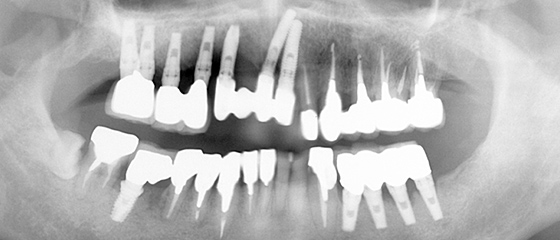

9ヶ月後

9ヶ月後に上顎の前歯に人工歯を装着しました。

治療後の経過

左下のインプラント撤去 →ブリッジ

治療後1年経過し、定期検診時に撮影したレントゲンで、左下のインプラントに骨吸収を発見したので撤去しました。その後、残りのインプラントをブリッジでつなげました。

歯根破折と根面う蝕で左上の歯を抜歯し、インプラント

1年後

右下クラウンが、虫歯により脱離し、保存不可能だったので抜歯しました。また、右上インプラントの動揺が出てきていたのでインプラントを撤去し、右上に3本、右下に2本のバイオホライズンズインプラントを埋入しました。

左上奥のクラウンが2本脱離

左上奥歯のクラウンが2本脱離してきたため、抜歯しインプラントをしました。

左下一番奥のインプラントの周囲骨が吸収して無くなっています。右上のインプラントはさらに位置移動が起こっています。

インプラント周囲炎が進行した左下奥歯のインプラントと、右上奥歯のインプラントを撤去しました。

右上のインプラントに対し2次手術を行いましたが、前方のインプラントは骨と結合しなかったため、インプラントを撤去しました。

また下前歯の虫歯が進行し保存不可能となった為、抜歯して上も下もインプラントのみで全ての咬合を再建するボーンアンカードブリッジにすることにしました。

下顎にインプラント埋入→連結

下顎のインプラントも連結しました。

長期間経過観察

インプラントの自然脱落が相次いだので、長期間経過観察をし、最終的な人工歯を装着しました。